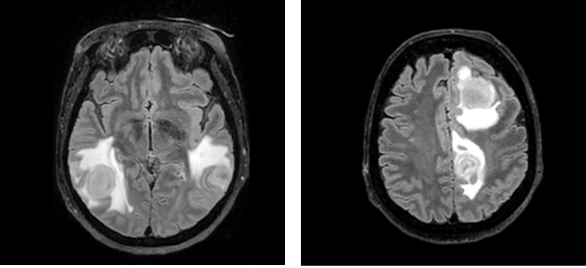

During elbow surgery, the patient experienced respiratory insufficiency, necessitating transfer to the Intensive Care Unit (ICU). Once stabilized, she was moved to the Neurology Department. Subsequent deterioration during a routine morning examination included nausea, diaphoresis, elevated blood pressure (220/90 mmHg), and tachycardia (heart rate 100 bpm). The worsening respiratory insufficiency led to her transfer to the Neurosurgical ICU and subsequent intubation. Despite normal laboratory findings, a chest CT revealed inflammatory infiltration and hypoventilation, but an infection was initially ruled out, precluding antibiotic administration. However, a repeated bronchoscopy culture isolated Proteus Mirabilis, sensitive to Cefuroxime, leading to a diagnosis of respiratory muscle weakness potentially related to myasthenia, and subsequent plasmapheresis was initiated. After extubation and initial stabilization, MRI revealed brain lesions to be consistently recognized as abscesses (Fig. 2).